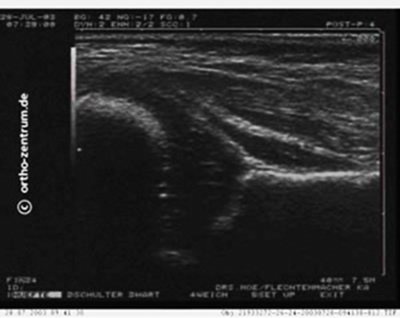

Ultraschallbild einer Hüfte eines 6 Wochen alten gesunden Kindes

Bei Neugeborenen und Säuglingen kann mit Hilfe der Sonographie eine Hüftreifungsverzögerung oder angeborene Hüftgelenkdeformierung nachgewiesen bzw. ausgeschlossen werden. Die Sonographie ist für die Säuglingshüfte deshalb so gut geeignet, weil keine Strahlenbelastung auftritt und auch knorpelige Strukturen gut darstellbar sind.

Das Skelettsystem des Säuglings ist nur teilweise knöchern, an vielen Stellen noch knorpelig ausgebildet. Eine Aussage darüber, ob die Formierung der Hüftgelenkspfanne und Überdachung des Hüftkopfes korrekt oder nicht ausreichend sind, ist zu diesem frühen Zeitpunkt mit Hilfe eines Röntgenbildes praktisch nicht möglich.

Durch die Entwicklung eines standardisierten Vorgehens bei einer Ultraschalluntersuchung kann man die Ausbildung der Überdachung und damit die Ausreifung der Säuglingshüfte korrekt beurteilen.